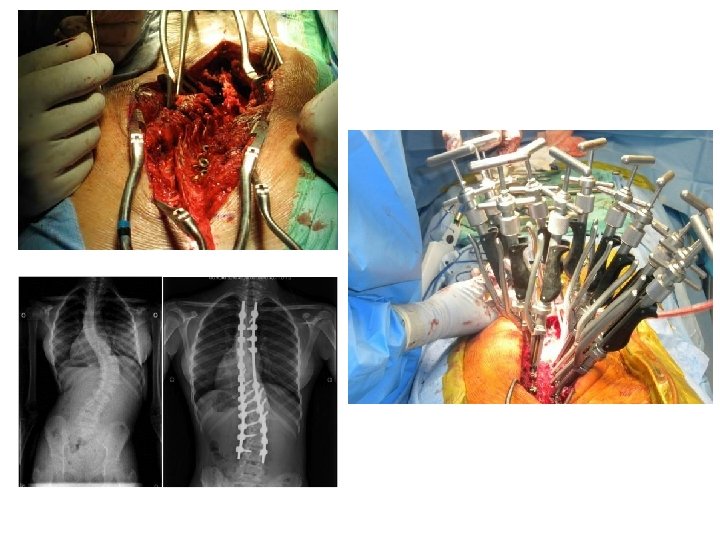

Scoliosis • Scoliosis is an abnormal curvature of the spine. If your child has scoliosis, the view from behind may reveal one or more abnormal curves. Scoliosis runs in families, but doctors often don't know the cause. More girls than boys have severe scoliosis. Adult scoliosis may be a worsening of a condition that began in childhood, but wasn't diagnosed or treated. In other cases, scoliosis may result from a degenerative joint condition in the spine.

Kyphosis • With kyphosis, your spine may look normal or you may develop a hump. Kyphosis can occur as a result of developmental problems; degenerative diseases, such as arthritis of the spine; osteoporosis with compression fractures of the vertebrae; or trauma to the spine. It can affect children, adolescents and adults.